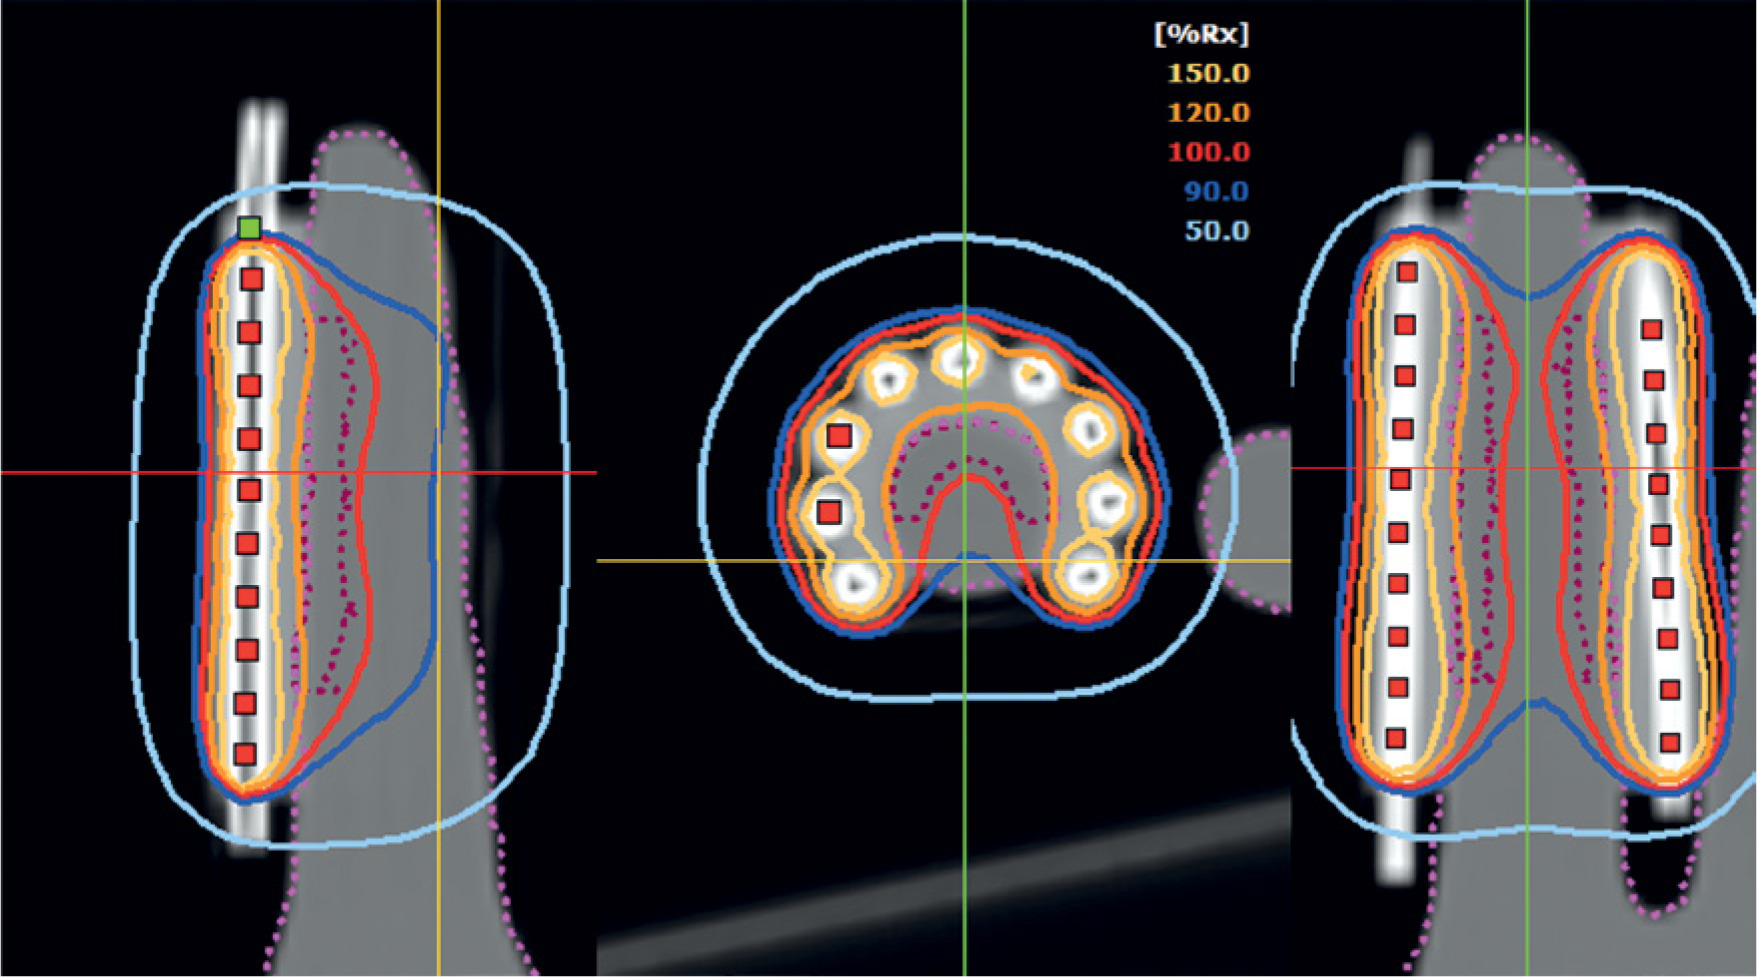

The symmetry of the applicator and equidistant arrangement of the catheters assured a favorable spatial distribution of the dose in the target volume. In addition, the modulation of stop times permitted for longer times to be assigned to both the catheters located at the ends of the assembly (the first and last) as well as to the initial and final positions within each catheter (Figure 5). This configuration provided greater control over dose conformation in peripheral areas, thus improving dose coverage around the treatment area. Additionally, the need to activate an additional stop beyond the last visible cut of the treatment volume in all catheters was identified. This decision helped to ensure complete coverage of the distal areas of PTV, avoiding regions with potential underdosing, which could compromise the treatment objective.

In terms of dose distribution, it was observed that most of the 120% isodose was located on the surface of the applicator, which was consistent with the dose gradient characteristic of surface configurations, where the dose on the skin tended to exceed the prescription [3, 21]. The maximum recorded surface dose reached 129% of the prescribed dose, a value within the ABS recommended threshold (ideally < 150%) and in line with ACROP (typical prescription depth 3-5 mm and approximately 130-135% surface for standard applicators), provided that critical structures were not involved and high-dose region was clinically tolerable [3, 15, 21]. On the other hand, the 100% isodose completely covered the volume defined as PTV, thus ensuring adequate coverage of the therapeutic target [15], as demonstrated in Figure 6.

Higher dose curves, such as 150% isodose were enclosed within the applicator, which can be verified by the dose-volume histogram shown in Figure 7, with no volume values observed for that dose. However, in the case of air between the surface of the applicator and the surface of the phantom, the dose on the surface of the finger should be increased, since the 100% curve tends to move further away from the applicator. For this reason, it is essential to ensure good adhesion between the applicator and the phantom’s surface.